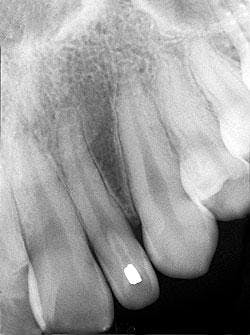

A review of the periapical films revealed a small radiopacity within the crown of the left maxillary lateral incisor (see radiograph). Clinically, the lateral incisor appeared small and peg-shaped. No other abnormalities were noted on the radiographs.

The dens invaginatus typically appears as a pear-shaped invagination of enamel and dentin within the crown and/or root of the tooth that closely approximates the pulp cavity. This in-folding of enamel can be easily recognized on a dental radiograph by its increased radiopacity - it resembles the radiodensity of enamel seen on the external surface of the tooth. Radiographically, the dens invaginatus appears as a small tooth-like structure within the affected tooth. The dens invaginatus is often associated with a periapical radiolucency because of the high incidence of pulpal death and necrosis.